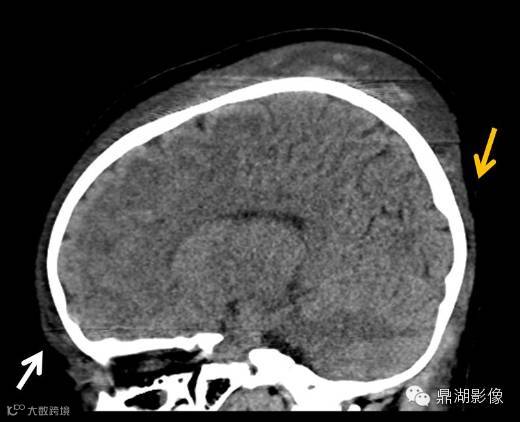

帽状腱膜下血肿多见于新生儿产伤。阴道自然顺产帽状腱膜下血肿的发生率为 0.4‰ ,负压吸引助产的发生率为 5.9‰ ,头皮牵引助产可损伤头皮与静脉窦之间的导静脉,从而导致帽状腱膜下血肿的发生。帽状腱膜下间隙的范围从前方的眶上缘,向后延伸到颈部后方,两侧到耳廓外侧的水平。帽状腱膜下间隙不受颅缝限制,因此大量出血可以在此聚集。血容量的大量丢失可导致休克及凝血障碍,死亡率为 14%。

帽状腱膜下出血是颅骨骨膜与帽状腱膜之间的疏松结缔组织出血。大量出血可聚积于帽状腱膜下间隙,使新生儿和儿童潜在的死亡风险增高。梳头时过于用力可致儿童帽状腱膜下出血,早期病因识别可以避免不必要的临床评价和干预,并排除虐童的可能性。